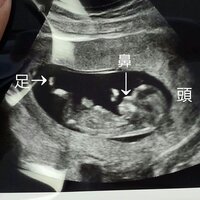

ダウン症のエコー特徴 手足 頭 Bpd Nt Fl徹底解説 Down And Up